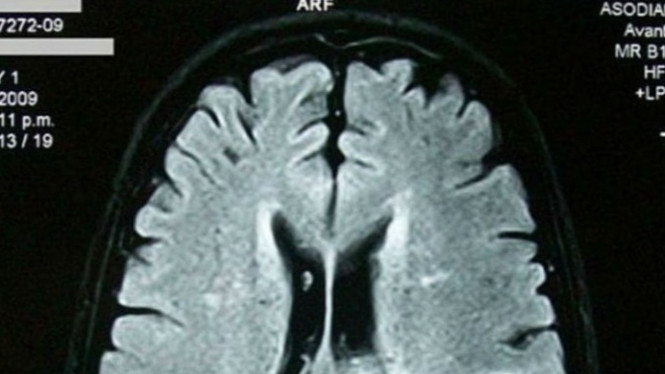

Jika kamu atau seseorang di sekitar mengalami gejala pendarahan otak, segera hubungi layanan darurat medis dan minta bantuan segera. Diagnosis pendarahan otak melibatkan tes medis, seperti CT scan atau MRI, untuk melihat kondisi otak dan memastikan diagnosis yang akurat.